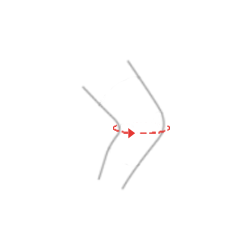

Istnieje możliwość zastosowania cieńszej poduszki pod zegar.